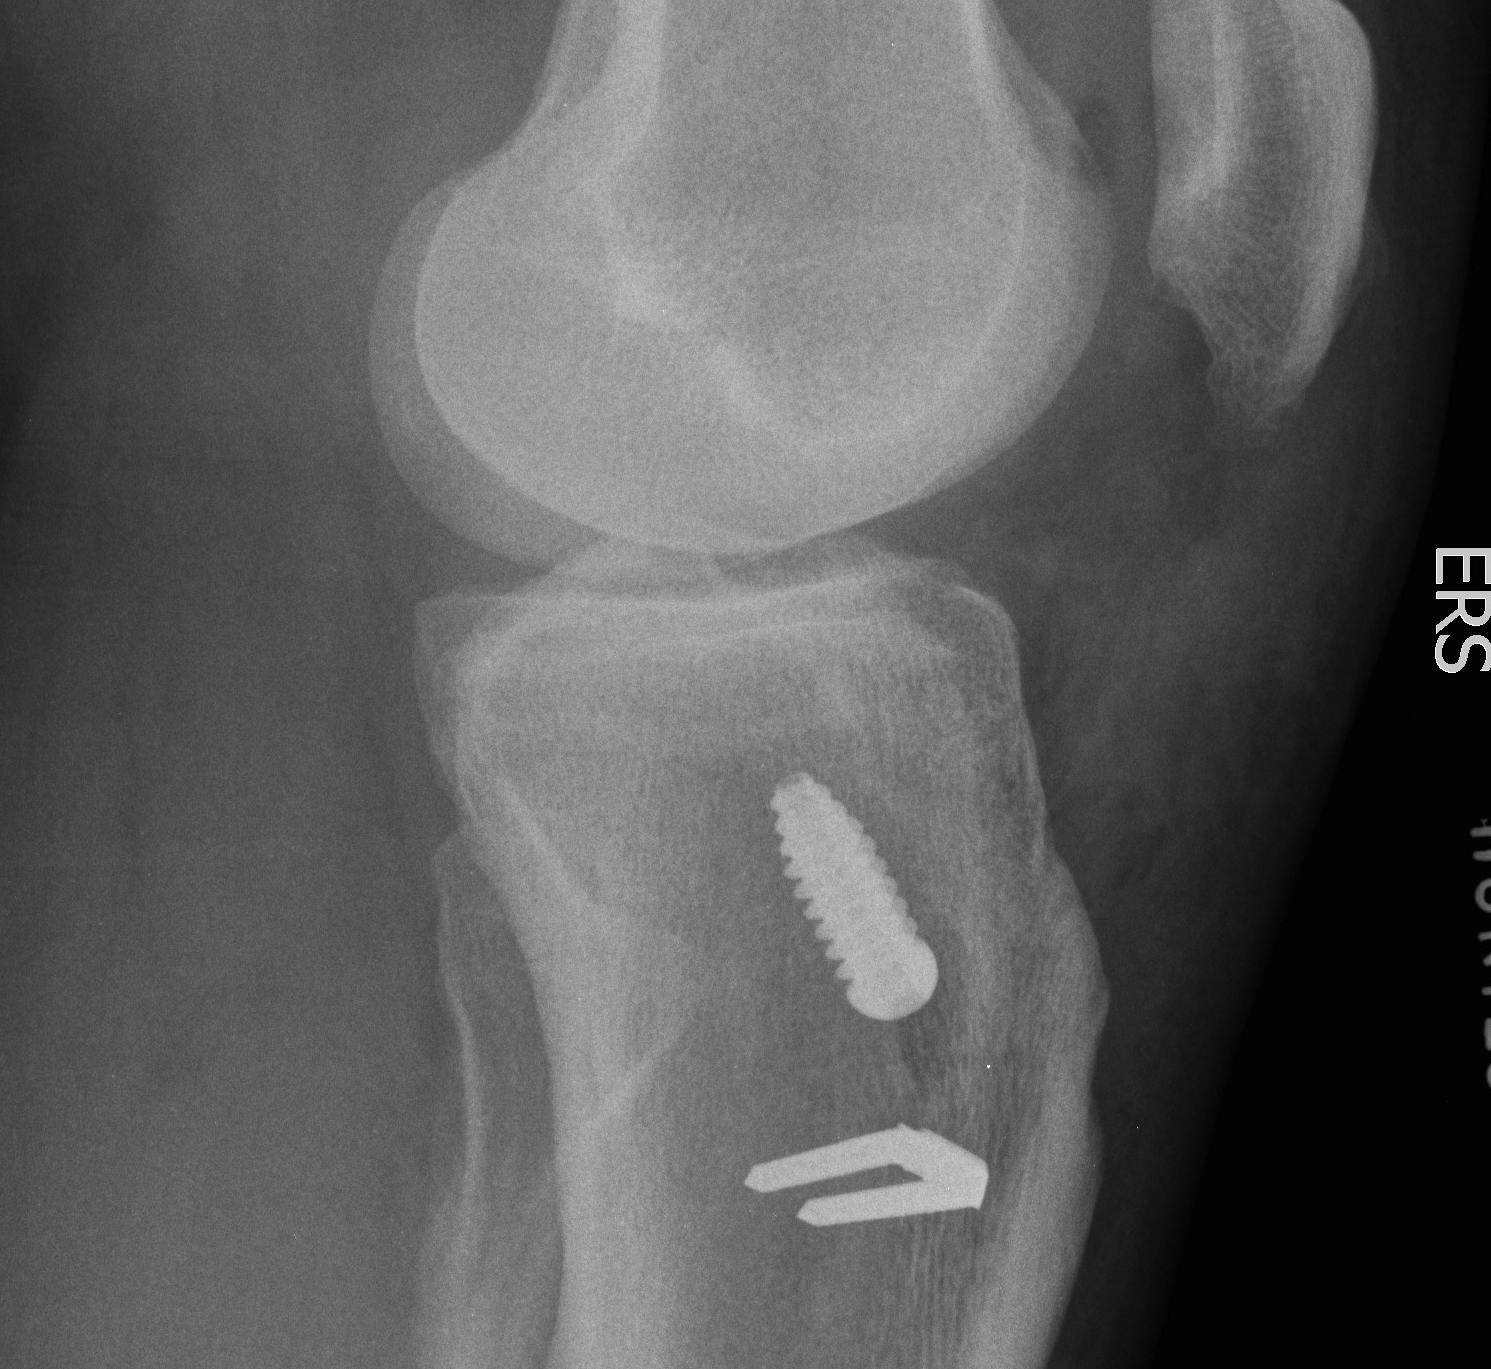

D. Graft Fixation Failure

Takes 6-12 weeks for graft incorporation to occur with hamstrings

Graft fixation needs to be strong for this period

E. Tunnel Lysis

Very common, cause unknown

No evidence that contributes to instability

Important in revision setting

Cause

- more common tibial side than femur

- tends to stop after 3/12

- postulated to be from synovial fluid pistoning

- hence fluid finds it easier to come down tibial tunnel as screw placed outside in

- also seen more on femoral side with endobutton (windscreen wiper effect)